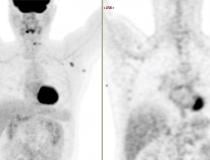

This photo gallery shows the variety of radiological presentations of COVID-19 (SARS-CoV-2) in medical imaging, including computed tomography (CT), radiograph X-rays, ultrasound, echocardiograms and magnetic resonance imaging (MRI). The radiology images show examples of typical COVID pneumonia in the lungs and the numerous complications the virus causes in the body in multiple organs, including the brain, kidneys, heart, abdomen and vascular system.

Ultrasound, especially hand-held ultrasound imaging devices, have become a primary imaging modality for novel coronavirus because of the ease to bag the device and sterilize it after use. CT and mobile X-ray systems are also used as front-line imaging systems for COVID-positive or suspected COVID patients.